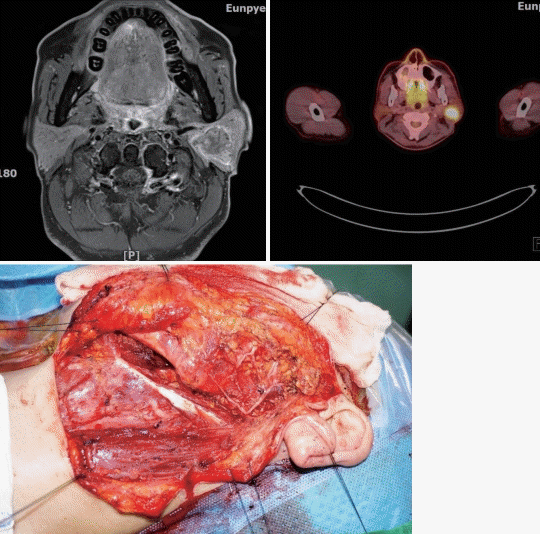

2. 56세 남자환자가 20년전부터 만져지던 좌측 이하부 종물이 최근 6개월전부터 크기가 증가해 내원하였다. 초음파 유도하 세침검사에서 악성 세포가 확인 되었다. 병기 설정을 위한 검사 후에 수술을 시행하였다. 수술 중 안면신경의 협가지(buccal branch)에 종양이 유착되어 있었고, 동결절편검사에서 악성세포가 확인되어 협가지를 절제한 후 대이개신경을 이용하여 재건하였다. 술후 병리 결과는 carcinoma ex pleomorphic adenoma with nerve invasion, vascular invasion이었다. 치료에 대한 설명으로 적절한 것은?

답 ②

해 설 수술 중 안면신경의 신경모니터링이 필요하기 때문에 수술 중에는 근육이완제의 사용을 피해야 하며, 수술 포를 덮을 때 수술 부위 쪽의 안면을 전부 노출시킨다. 변형 blair 절개, 얼굴성형절개, 이개후두발선절개, 이개주위절개가 있으며 악성인 경우에 림프절 절제술을 하기 위해서는 변형 blair 절개를 주로 한다. 안면신경 줄기를 찾기 위해 이용하는 해부학적 지표로는 이주연골지표, 고실유동봉합, 후이복근의 근육 부착부위, 신경분지 말단으로부터의 역행성 박리, 유양동 내의 신경 등이 있다. Frey 증후군을 예방하기 위해 천근건막체계, 흉쇄유돌근, 진피 혹은 진피지방, 대퇴근막, 측두두정골근막등을 사용하여 기계적인 장벽을 형성할 수 있으며 천근건막체계나 흉쇄유돌근을 가장 많이 사용한다. 수술 후 병리 소견에서 진행된 병기, 절제연 미확보, 고악성도 종양, 신경 침범, 림프관/혈관 침범이 있으면 방사선 치료의 적응증이 된다.

참고 문헌: 대한이비인후과학회. 이비인후과학:이과. 파주: 군자출판사;2018. p.373-7.